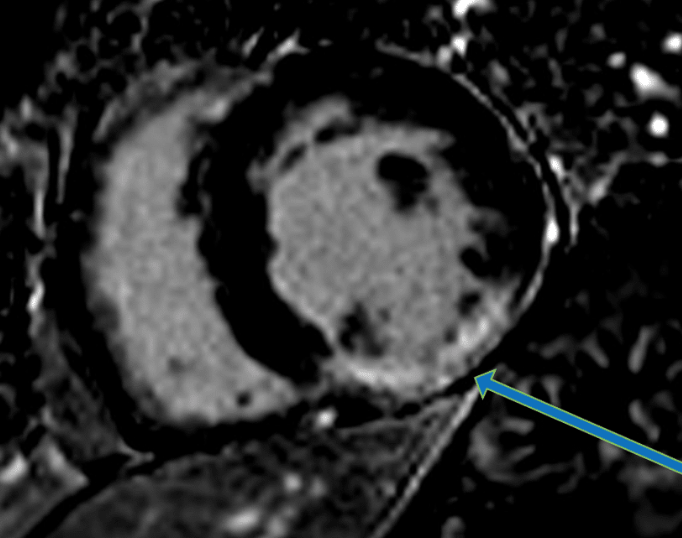

Nach aktuellem Forschungsstand gilt die Magnetresonanztomographie des Herzens (Kardio-MRT oder auch Herz-MRT) aktuell als die genaueste Methode zur Beurteilung der Morphologie („Herzarchitektur“) und Funktion („Herzkraft“) des Herzens und des Herzmuskels.

Die Kardio-MRT ist mittlerweile als Referenzstandard zur Beurteilung der Funktion und der Durchblutungsmessung wissenschaftlich und klinisch (europäische Leitlinien der ESC) anerkannt und somit zuverlässig verwendbar.